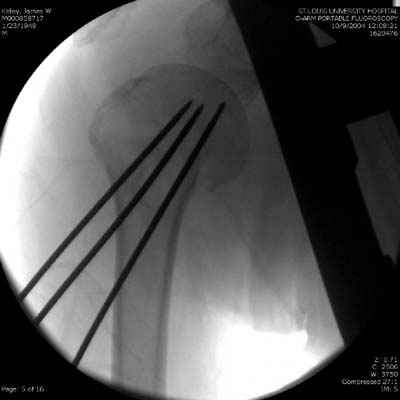

Посылаю послеоперационные Рг граммы.

Поздравляю, получилось просто замечательно. Если можно, расскажи чуть подробнее, как делали - как вправляли, как вводили спицы, поворачивали ли их?

Спасибо за поздравления:-))

Я и сам доволен результатом. В предпоследнем письме я кратко описал ход операции - закрыто репонировать не удалось( 2 недели с момента травмы и 1 неделя после неудачной репозиции) после удаления пучков спиц, пришлось сделать - 2см разрез на уровне перелома и с помощью периостального элеватора (золотое правило механики) *одеть* головку на дистальный отломок.

Спицы проводил через старые отверстия, вращая пучок импактором- направителем при его введении в головку.

Женя, привет. Все правильно - молодец. По моему у тебя в презентации должен быть слайд с набором инструментов. Несколько советов - ушко должно быть больше 6 мм - около 8 мм в диаметре, перед введением спиц мы разводим концы - как бы заряжая пружину, вводим конца в канал с помощью риноскопа, но после введения дбиваем спицы через кондуктор для шейки бедра, который имеет внутренний диаметр 10 мм. Всего наилучшего! ЛАФ.